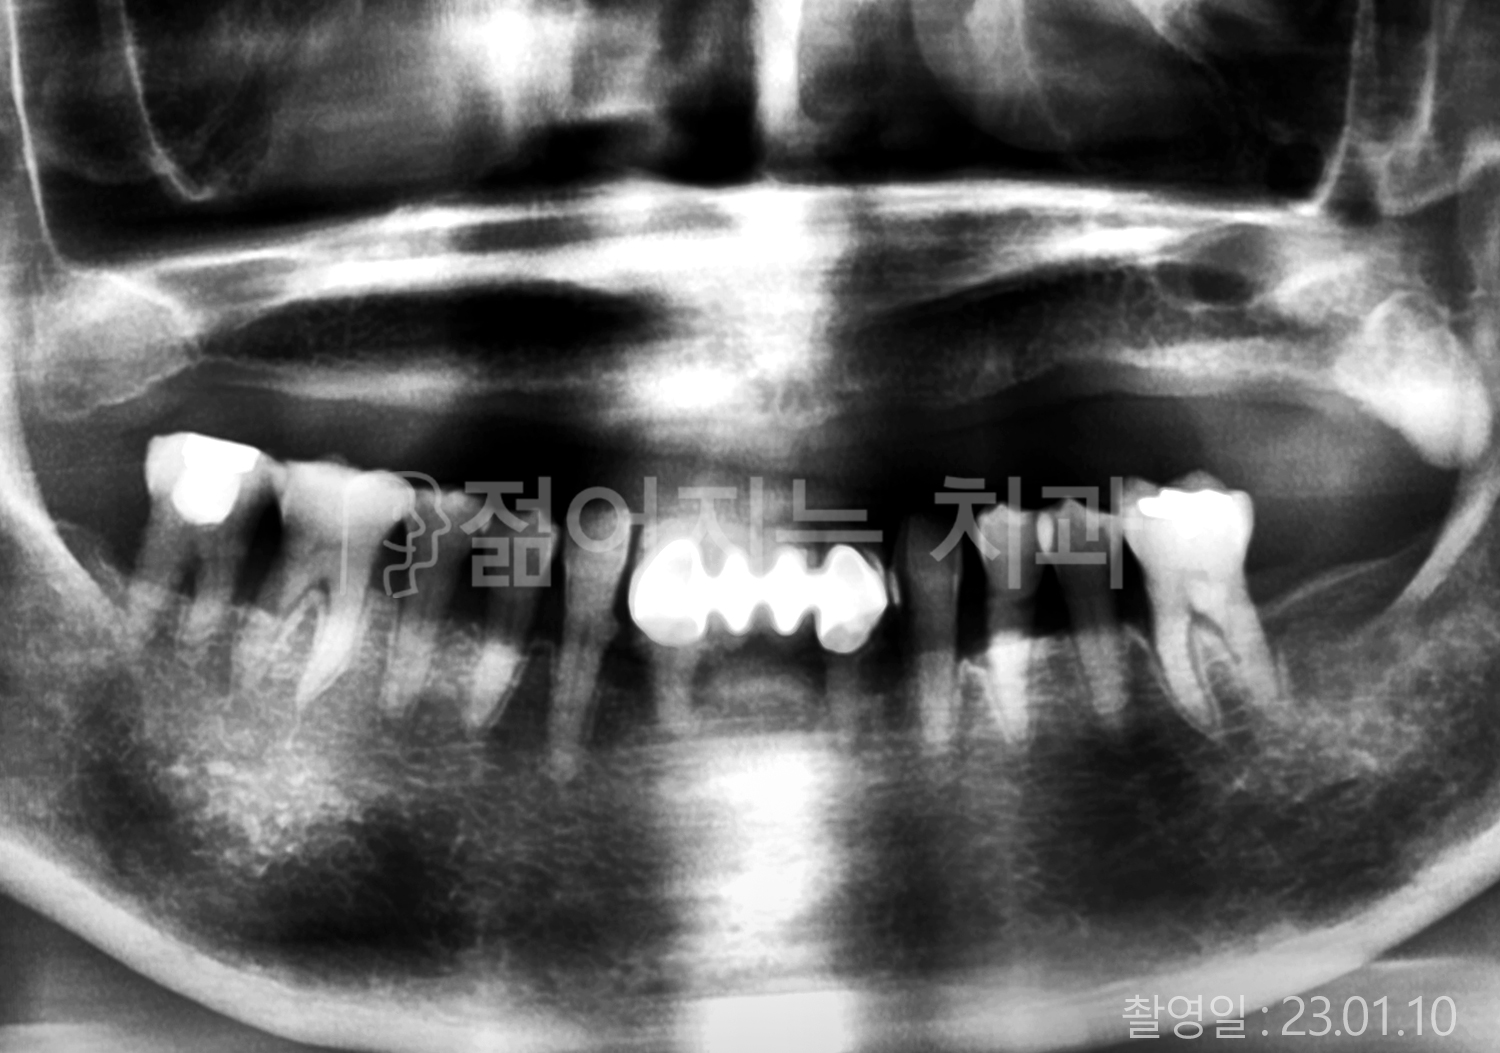

• 80대 전체치아 10개 이상 임플란트

• 60대 고혈압, 당뇨, 고지혈증 전체치아 10개 이상 임플란트

• 60대 전체치아 10개 이상 임플란트

• 60대 고혈압, 고지혈증 전체치아 10개 이상 임플란트

• 50대 고혈압, 당뇨, 고지혈증 전체치아 10개 이상 임플란트

• 70대 골다골증, 파킨스병 전체치아 10개 이상 임플란트

• 40대 전체치아 10개 이상 임플란트

• 60대 골다골증 전체치아 10개 이상 임플란트

• 40대 고혈압 전체치아 10개 이상 임플란트

• 50대 전체치아 10개 이상 임플란트

• 70대 전체치아 10개 이상 임플란트